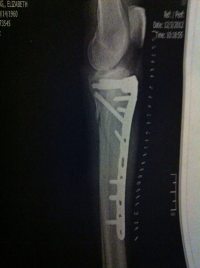

To make this long story shorter, I finally had surgery and this is how it all looks today:

Xray of Betsy's leg

I'm walking with a brace and a cane and getting around pretty well. And, yes, I intend to get back on my motorcycle. This time with a hard lesson learned and a better idea of what can happen when you don't pay attention.